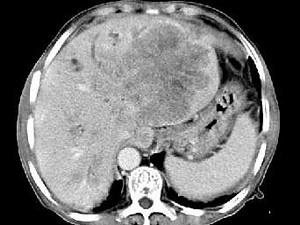

问题 女,73岁,中上腹痛一月余,患者黄疸、消瘦,CT检查如下图,最可能的诊断是 ( )

选项 A、肝淋巴管瘤 B、肝胆管细胞癌 C、巨块型肝癌 D、肝血管瘤 E、肝脓肿

答案 C